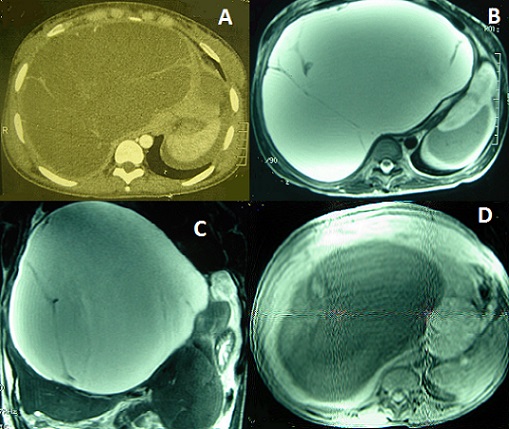

Les cystadénomes hépatiques sont des tumeurs kystiques rares et de diagnostic pré-opératoire difficile en imagerie. Ils touchent le plus souvent des femmes de plus de 50 ans. Une attitude chirurgicale radicale, compte tenu du potentiel malin de ces lésions, est recommandée. Nous rapportons le cas d'une patiente âgée de 22 ans qui a été opérée il y a 4 mois dans un hôpital régional à tort pour kyste hydatique du foie, mais en peropératoire vu l'aspect, il n'a pas été réalisé de geste. La biologie hépatique était normale. La tomodensitométrie abdominales avait ojectivé une masse kystique multiloculaire de 25X13 cm avec des cloisons épais de 3 à 5 mm de diamètre évoquant un kyste hydatique de type III ou un cystadénome biliaire. L'IRM abdominale a objectivé une masse kystique cloisonnée bien limitée du foie droit mesurant 23X23X21 cm en hypersignal homogène T2, hyposignal T1 avec des cloisons non rehaussés après injection de Gadolinium, aspect en faveur d'un cystadénome hépatique. La sérologie hydatique était négative. Il a été réalisé dans un premier temps une liguature portale droite à fin d'entrainer une hypertrophie compensatrice du foie gauche en vue d'une résection hépatique droite. Lors de la deuxième opération, il a été réalisé une kystectomie subtotale, avec coagulation de la partie résiduelle, en raison des adhérences entre le kyste et les structures vasculaires cavo-sushépatiques. L'examen anatomopathologique avait confirmé le diagnostic de cystadénome hépatique. Les suites opératoires ont été simples et avec un recul de deux ans, il n'a pas été noté de récidive.